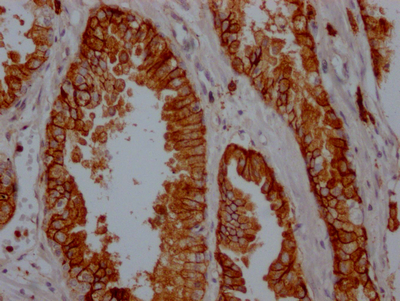

ELISA, WB, IHC, FC

ELISA, WB, IHC

ELISA, IHC, IF, FC

| BTK | BTK Recombinant Monoclonal Antibody | Human | ELISA, IHC | CSB-RA553167A0HU |

| C3 | C3 Recombinant Monoclonal Antibody | Human | ELISA, WB, IHC, FC | CSB-RA303909A0HU |

| C3 | C3 Recombinant Monoclonal Antibody | Human | ELISA, IHC | CSB-RA699863A0HU |

| C5 | C5 Recombinant Monoclonal Antibody | Human | ELISA, FC | CSB-RA003995MA1HU |

| EGFR | EGFR Recombinant Monoclonal Antibody | Human | ELISA, WB, IHC, IF, FC | CSB-RA159341A0HU |

| EGFR | EGFR Recombinant Monoclonal Antibody | Human | ELISA, WB, IHC | CSB-RA794061A0HU |

| EGFR | EGFR Recombinant Monoclonal Antibody | Human | ELISA, IHC, FC | CSB-RA159341MA1HU |